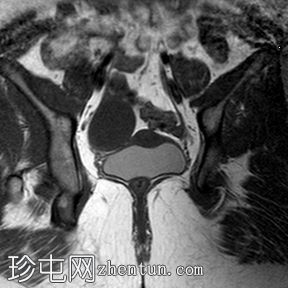

轴位

T1加权像

阴道明显扩张,T1加权像呈中高信号,T2加权像呈高信号,耻骨联合下方可见一小局灶性隆起。

左侧卵巢大小正常,可见一小出血性囊肿。

盆腔内可见少量游离液体。